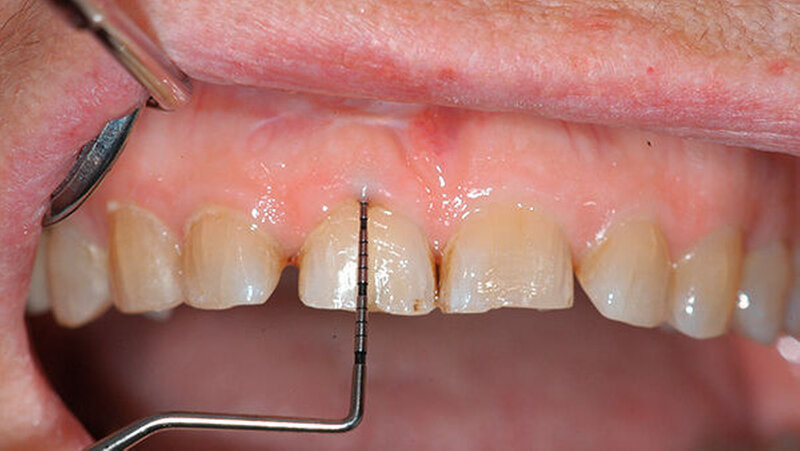

Sowohl klinisch als auch röntgenologisch zeigte sich nach der Behandlung ein erfolgreich replantierter Zahn (Abbildung 8). Bereits nach dreimonatiger Einheilungsphase reduzierte sich die Taschensondierungstiefe von 7 mm auf 3 mm (Abbildung 9).